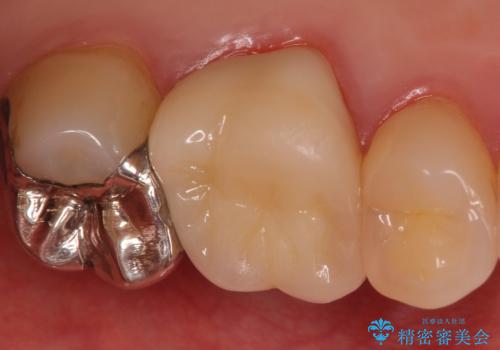

割れた被せ物を作りなおしたい

- 他院で装着した被せ物が割れたとのことで来院されました。

被せ物の厚みが確保されていなかったため、向かいの歯とのスペースを確保するように修正していきます。

被せ物の厚みが十分に確保できていないと、材料によっては今回のように割れてしまうことがあります。

被せ物の材料を変えるか、厚みを確保することでそのリスクを抑えることができます。

今回はセラミックでの再治療をご希望されたため被せ物の厚みを確保することで対応しました。